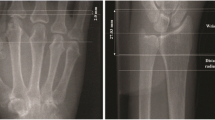

Participants attended baseline and 12-month in-person evaluations. Physical Evaluations: Measures of height (cm) and weight (kg) [Body Mass Index (BMI): Kg / m2] were collected for all participants and a 28-joint active (Tender and Swollen) joint count for RA participants [32]. Self-Reported Measures: Participants completed a General Health and Lifestyle questionnaire. RA participants also completed a Stanford Health Assessment Questionnaire - Modified (mHAQ) [33]. HR-pQCT Imaging: The imaging protocol has been described in detail elsewhere [19]. Briefly, we acquired HR-pQCT images with a Scanco XtremeCT imaging system [Scanco Medical AG, Switzerland] using standard manufacturer recommended parameters [19]. For the radius, the reference line was the medial/distal radius (Fig. 1a – Scout View). The scan started 3 mm proximal to this reference line and extended 9.02 mm (110 slices) proximally (Fig. 1a – Scout View). For the metacarpal head the reference line was the tip of the most distal second or third metacarpal head. The scan started 4 mm distal to this reference line and extended 18.04 mm (220 slices) proximally [19, 20]. (Fig. 1a -Scout View). Each 110-slice scan takes 2.8 min with an effective dosage of less than 2 μSv [19].

a 150 mm Scout View Image. Dots = Reference points for the distal radial (medial distal cortex radius) and metacarpal head (distal tip of most proximal MH) scans. Larger shaded boxes = Distal Radius (110 slices) and Metacarpal (220 slices) scan lengths. Smaller boxes with UUD, MH2 and MH3 text = Three Regions of Interests (ROIs) evaluated (UUD = Ultra-ultra distal, MH = Metacarpal head 2 or 3). b Single HR-pQCT image slices of a cross-sectional image of MH (Top) and Distal Radius (Bottom) scans. Lines show cortical bone periosteal and endosteal semi-automatic segmentation. c 3-Dimensional reconstructed images of MH (top) and UUD (bottom) scans of a non-RA participant, with the cortical bone and trabecular bone regions separately reconstructed